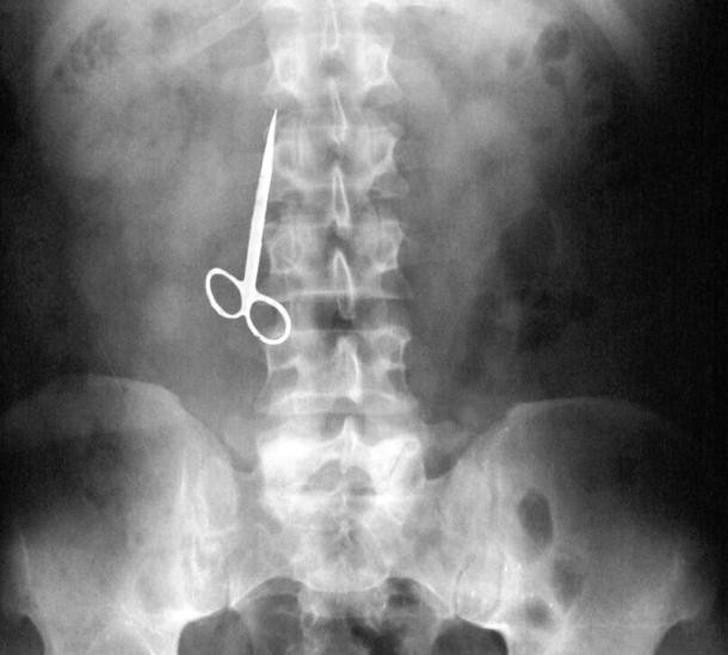

24. Ножницы.